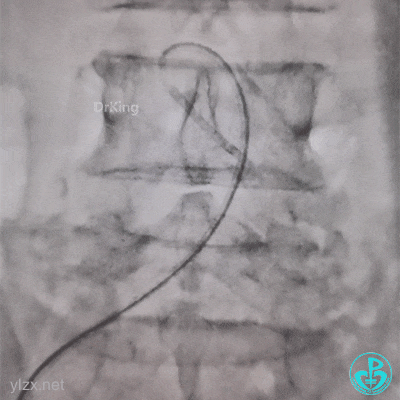

糟糕,打折了,想解开,重新换管子。

结果上面又出问题。

管子反折,J-W根本无法通过。